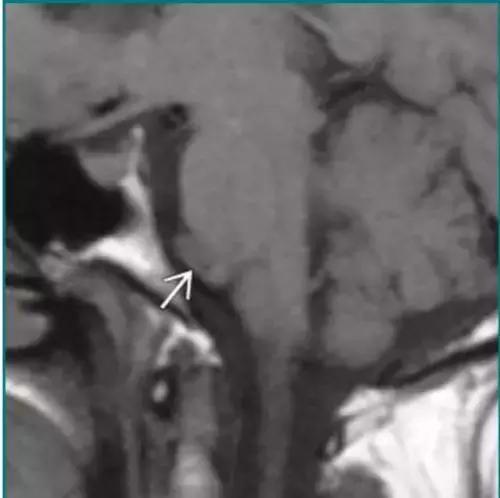

神经肠源性囊肿